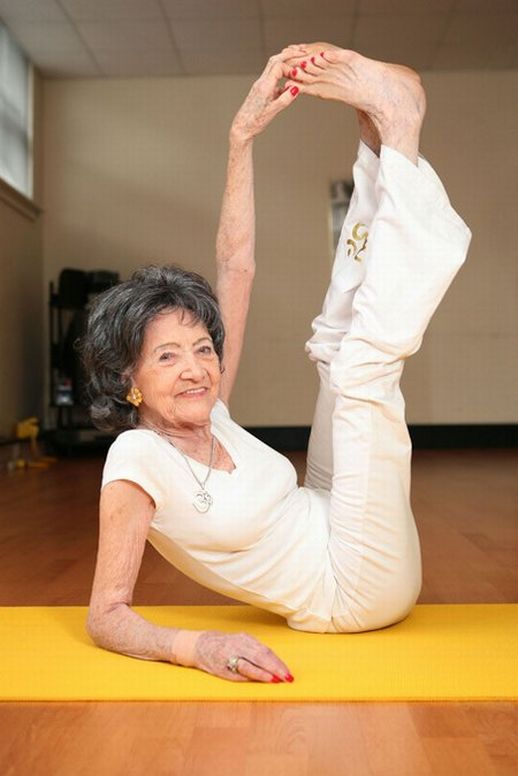

Grazie a Hondro Sol, più di 17.000 persone in Italia hanno evitato l’invalidità e recuperato la libertà di movimento. Ecco alcuni pazienti del professor Silvio Garattini:

— Tutte queste foto dimostrano che “Hondro Sol” restituisce salute alle articolazioni anche in quei casi in cui la diagnosi sembrava una condanna. Senza operazioni, senza dolore insopportabile — tutti i pazienti hanno ottenuto un miglioramento duraturo e sono tornati a una vita piena. QUESTO RIMEDIO HA CAMBIATO COMPLETAMENTE IL CORSO DEL TRATTAMENTO DELLE ARTICOLAZIONI E DELLA COLONNA VERTEBRALE!

Prima avevo dolori costanti alla schiena e le gambe mi cedevano, ma Hondro Sol ha cambiato tutto! Non avrei mai pensato di poter fare yoga e vivere attivamente a 68 anni! Dio benedica i creatori di questo rimedio!